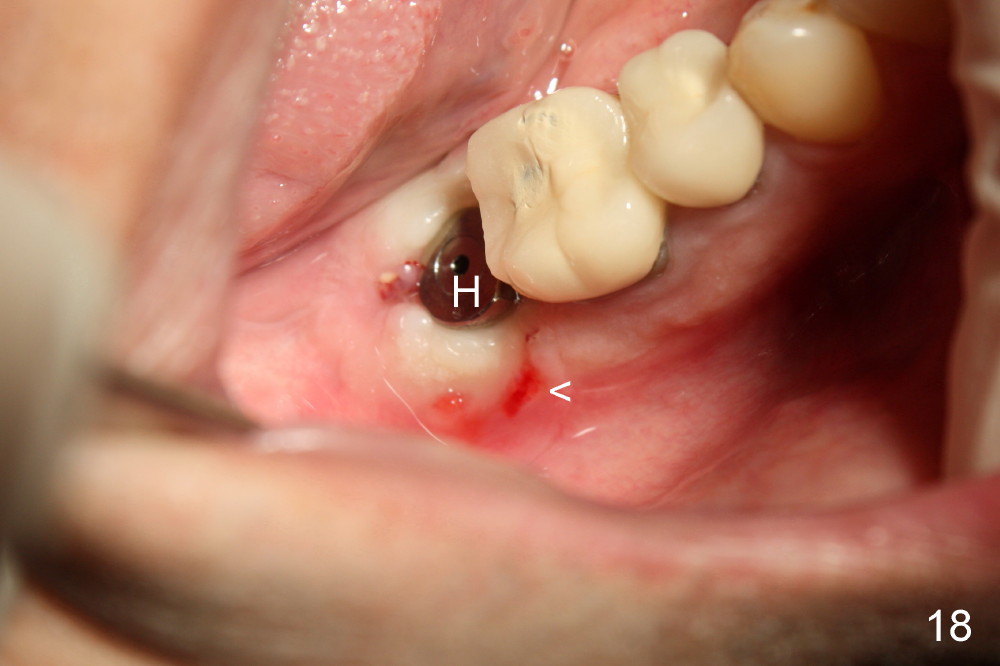

Four months postop, there is a sign of osteointegration (Fig.16 <). Graft particles migrate to the surface of the mucosa (Fig.17 <). A healing cuff is placed over the implant for preparation of restoration (Fig.18 H); graft particles are removed (<). Due to insurance issue, the restoration is yet to finish by 6 months postop (Fig.19 C: healing cuff); the cystic lesion appears to have been decreased concentrically (*). The bone density in the former cyst area continues to increase 14 and 32 months postop (Fig.20 A: abutment; Fig.22). Small piece of bone graft (<) is being extruded distobuccal to the #31 crown (C) asymptomatically 15 and 32 months postop (Fig.21,22).